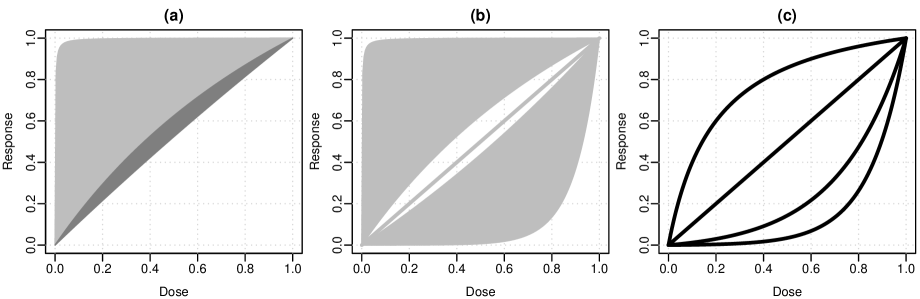

The middle plot of Figure 2 illustrate this construction for the exponential model with for . Here and in the following, we will write and for the -th elements of the vectors and . Assume that we observe a point . The correlation is maximized when . Four points , which are equally spaced on , are shown together with their spherical caps; the tubular neighborhood is generated by moving the spherical cap along the curve . Note that equal spacing of points on leads to unequally parameter values , this is due to the nonlinearity of the model function.

Since is invariant under affine transformations of and , we may scale them to the unit interval (``zero-one standardization''), as shown in the left-hand side of Figure 2.

2.2.3 critical values

Before we continue to the case of multiple models in the next section, we will consider what could happen if we would simply ignore the identifiability issue and would assume that the statistic is asymptotically distributed.

The critical value of such a test would depend only on the number of parameters in the model, but not on the area of on sphere covered by the model. One can construct an example that shows that such a test can not control the type-I error in general: in fact, for any critical value of the statistic , there exists a model so that the resulting test always rejects (has type-I error 1). The idea is to choose the model in such way that the standardized predictions form a curve that comes arbitrarily close to any point on the unit sphere. In Appendix B we give the model equation for a model function that fulfills these requirements, see also the right-hand side of Figure 2, which gives a graphical illustration of this model.

To observe the impact of the richness of the candidate set on the critical value (i.e. the resulting multiplicity adjustment), we will sequentially increase the set of candidate models. We start with the Emax model , where the interval was chosen for the parameter . This interval covers a wide range of possible shapes underlying the Emax model. This can be seen, when plotting and overlaying the resulting (``zero-one'' standardized) response curves; see Figure 4 (a). The boundaries of the polygon correspond to equal to and . When using a significance level of 5% one-sided, the resulting critical value is . When raising the upper limit of to , although this results in a much larger interval for , the critical value only goes up to . The reason is that the standardized model predictions do not cover much additional area on the unit sphere. This can also be seen in Figure 4 (a) in the dark gray area: Due to the nonlinearity, the additional flexibility on the parameter space (by increasing the upper bound to 10) does not lead to a major increase in flexibility of the model shapes.

Now suppose we would like to add a linear model to the candidate set of models. The linear model does not use a dose transformation and it represents only a single shape; see also the linear increasing line in Figure 4 (b). Therefore, adding this model does not make the candidate set much broader in terms of shapes, and the critical value only increases to . When adding an exponential model of form with parameter bounds , this leads to a more pronounced extension of the possible predictions. This is also reflected in the critical value, which goes up to . Figure 4 (b) shows the possible shapes that will be used for the LR test.

So there is a direct, intuitive connection between the critical value and the complexity of the candidate model shapes. The more parts of the unit sphere are covered the larger the multiplicity penalty. On the other hand, when an additional shape is added that is similar to other shapes that are already in the candidate set, the critical value does not increase noticeably, due to the overlap of tubes.

For comparison we will also apply the MCP-Mod procedure. Similar to Bretz et al. (2005), we choose an Emax shape with , a linear shape and two exponential shapes, one with and the other with . The candidate shapes of the MCP-Mod procedure are presented in Figure 4 (c). The results shown in Table 2 have been calculated using the MCTtest function in the DoseFinding package. One can see that the Emax and linear model have p-values similar to the LR test. However, the two exponential shapes have p-values , despite the fact that a trend could be detected using the LR test for the exponential model. The reason is that neither of the two values fits the data well. If the exponential model for would have been included in the set of MCP-Mod candidates also a p-value smaller than would be observed.